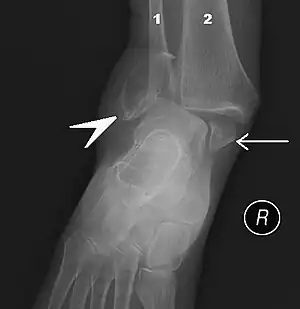

The initial evaluation of suspected ankle pathology is usually by projectional radiography ("X-ray").

For ligamentous injury, there are three main landmarks on X-rays: The first is the tibiofibular clear space, the horizontal distance from the lateral border of the posterior tibial malleolus to the medial border of the fibula, with greater than 5 mm being abnormal. The second is tibiofibular overlap, the horizontal distance between the medial border of the fibula and the lateral border of the anterior tibial prominence, with less than 10 mm being abnormal. The final measurement is the medial clear space, the distance between the lateral aspect of the medial malleolus and the medial border of the talus at the level of the talar dome, with a measurement greater than 4 mm being abnormal. Loss of any of these normal anatomic spaces can indirectly reflect ligamentous injury or occult fracture, and can be followed by MRI or CT.[27]